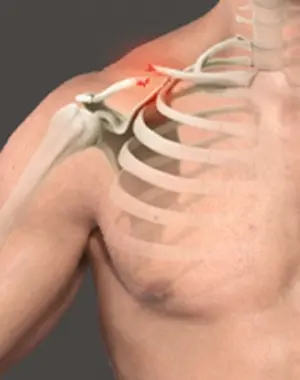

Clavicle Fracture

Shoulder Fracture

Shoulder Fracture Care